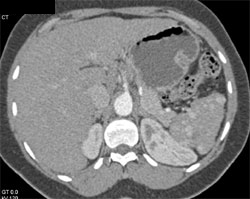

Sickle Cell Disease